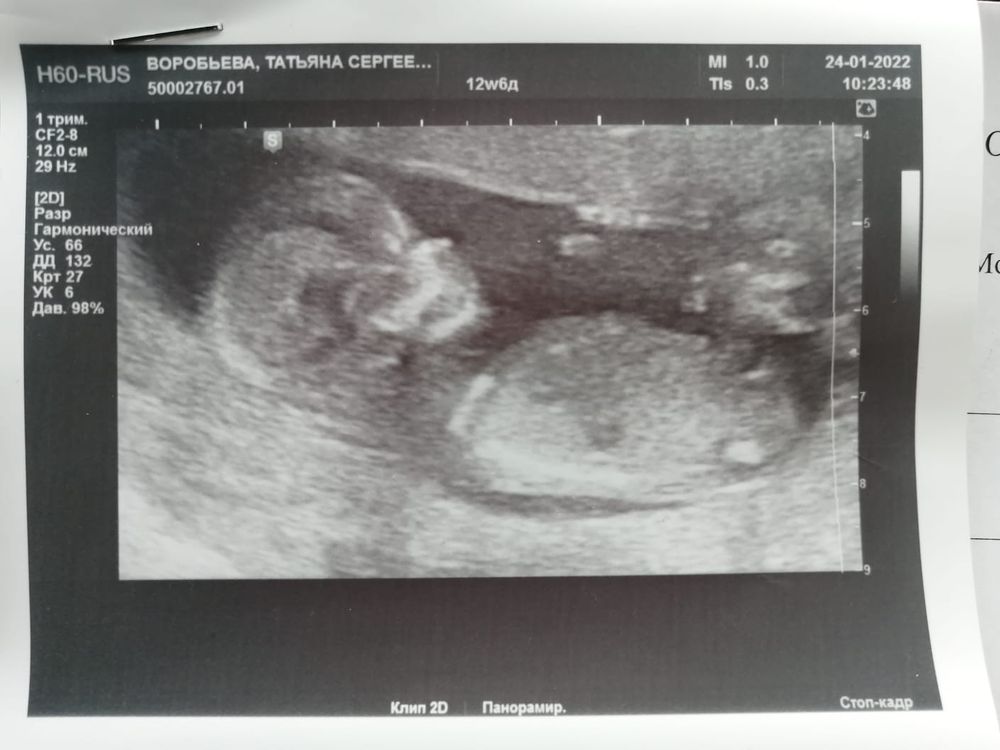

Первый скрининг, 12+6 недель

В итоге по УЗИ все хорошо. КТР мой любимый уже 7,3 см, то есть уже опережает на 4 дня срок. Остальные цифры - ТВП 1,7 мм, БПР 23 мм, ОЖ 62,9 мм, ЧСС 153 уд/мин, носовая кость определяется (сказали, что длинная).

Фото малыша для истории. Такой милый, двигал ручками, ножками, переворачивался. Хорошо там тебе, тепло. Расти, мой хороший.